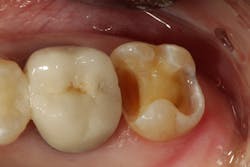

A second molar presents with an old leaking, large class II restoration that has been previously repaired and has radiographic recurrent decay (figure 5). In an ideal world, this tooth would be best served with a core buildup and full-coverage crown. However, due to financial considerations, the patient requests restoring with the less expensive option of a composite restoration.

The exceptional physical properties of GrandioSO make it an excellent choice for the demands that will be placed on this restoration.

The old restoration is removed with an 845KR diamond bur. Decay is excavated using a slow-speed round bur and confirmed using a caries detection agent (Seek, Ultradent; figure 6).